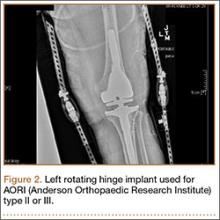

4. Rotating hinge designs

Many patients who undergo revision TKA can be managed with a posterior stabilizing or nonlinked constrained design. However, in patients who present with severe ligamentous instability and bone loss (AORI type II or III), a rotating hinge prostheses, or highly constrained device, is often recommended (Figure 2).18 By using a rotating mobile-bearing platform, this prosthesis permits axial rotation through a metal-reinforced polyethylene-post articulation in the tibial tray. In addition, it involves use of modular diaphyseal-engaging stems and diaphyseal sleeves, which allow for the bypass of bony defects and areas of bone loss (Table 2).

However, the rigid biomechanics of hinged prostheses is associated with increased risk for aseptic loosening (aseptic 10-year survival, 60%-80%), imparted by the transfer of stresses across the bone. The higher risk for early loosening, osteolysis, and excessive wear—caused by the highly restricted biomechanics of early generations of fixed hinged designs—has led to the development of new devices with mobile mechanics. Prosthetic designs have been improved with an added rotational axis to reduce torsional stress, a patellar resurfacing option, and better stem fixation and patellofemoral kinematics. Overall, these are aimed to improve rates of instability and aseptic loosening, with promising results demonstrated in the literature.